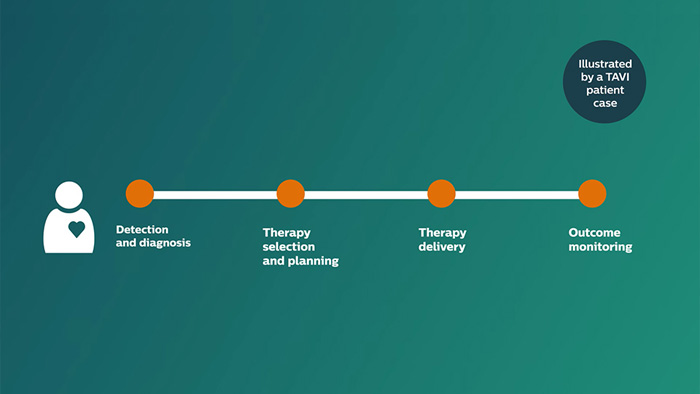

El recorrido de un paciente que recibe una valvuloplastia aórtica con catéter (transcatheter aortic valve implantation, TAVI) con IntelliSpace CardioVascular